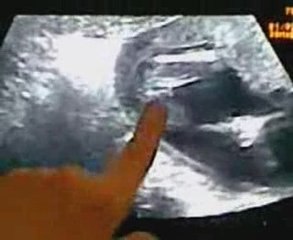

FILM échographie du 09 mars 2009.

Echographie en film Manu le 09 mars 2009.